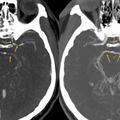

Zožitev arterij

Čili: Po zaužitju popularne zelenjave so ga odpeljali na urgenco

Računalniška tomografija glave pokazala, da so se moškemu močno zožile arterije.